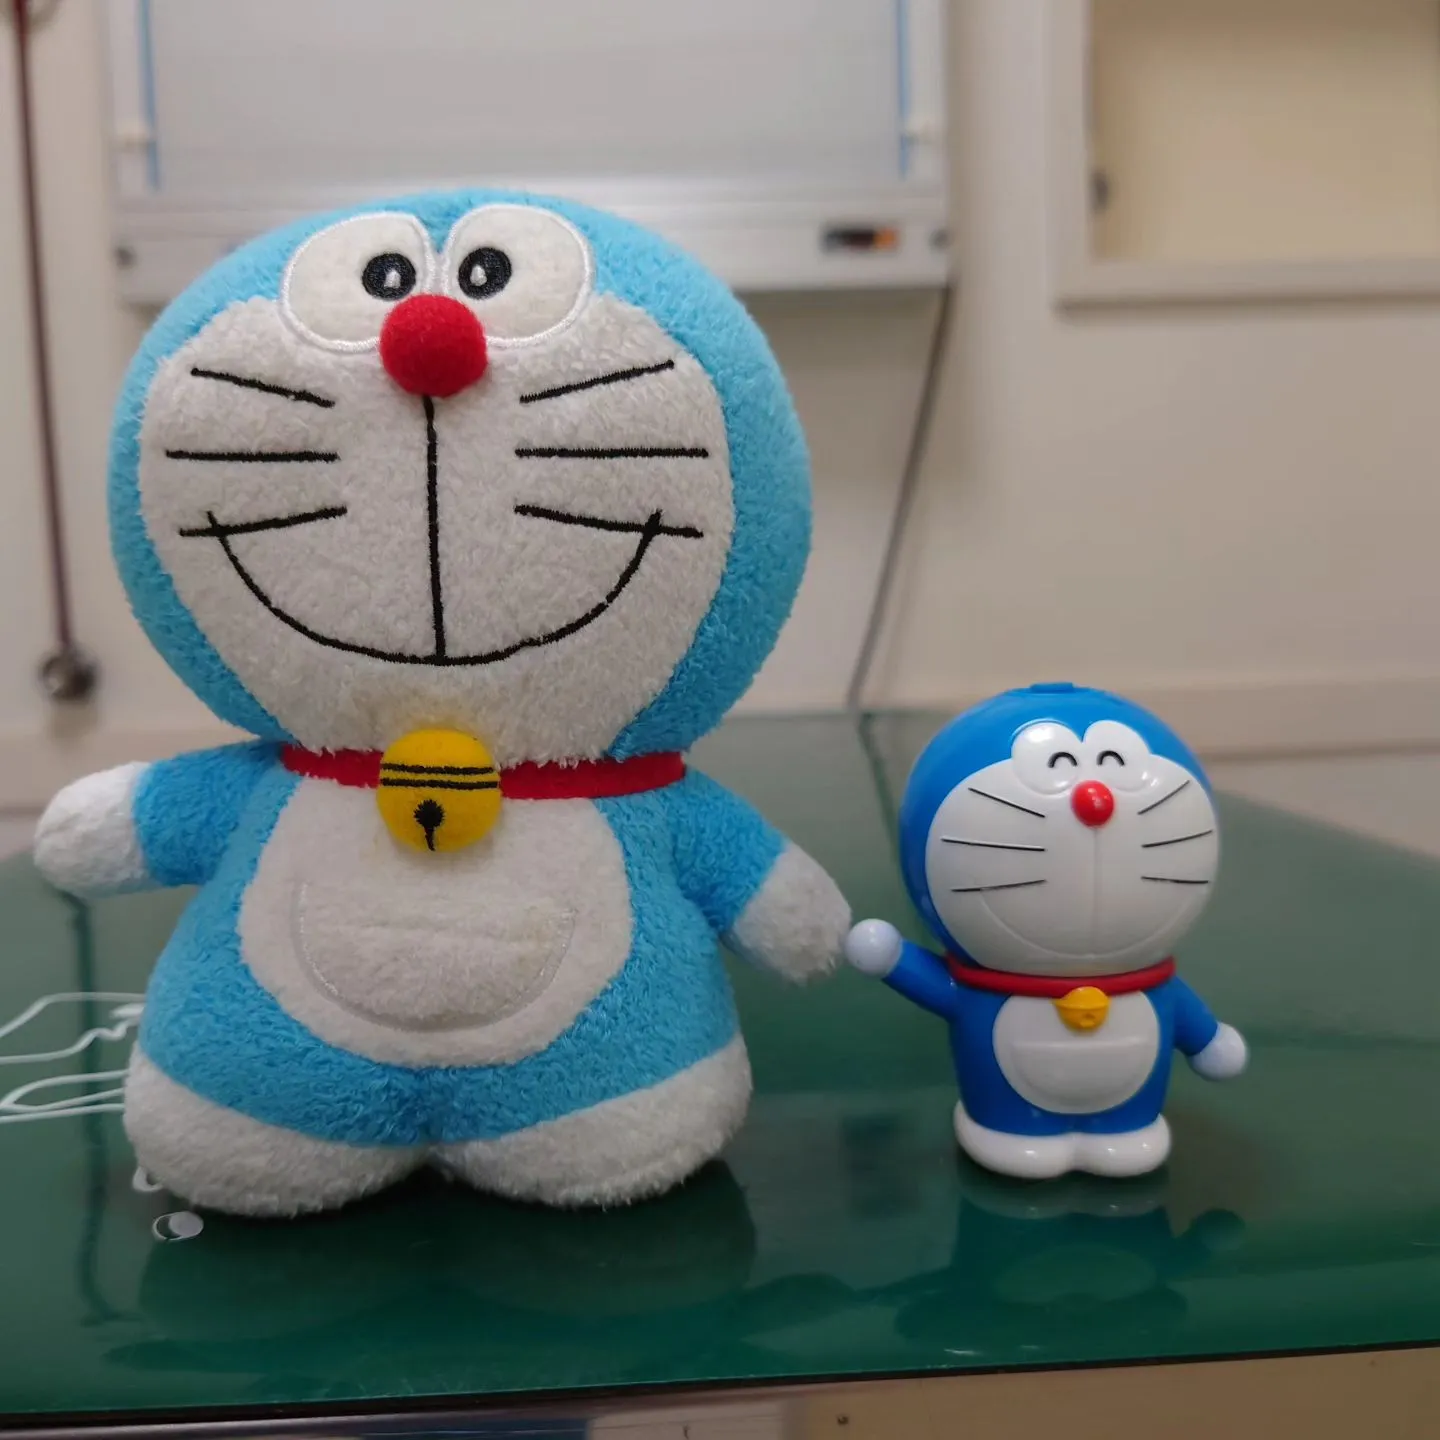

写真は、ぬいぐるみとプラスチックのドラえもんのレントゲンです。金属ねじははっきりとわかりますが、ドラえもんの形など細部はぼんやりしており、写りにくいです。

【失敗】私の想定よりもぬいぐるみドラえもんが写ってしまいました。